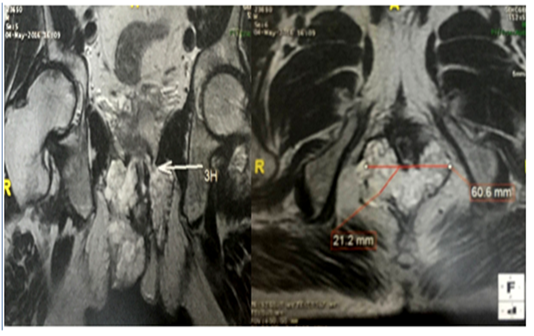

We report a case of a 44-year-old patient with a 20-year medical history of CD. He underwent ileocecal resection at age of 22 years. He had poor treatment adherence and a lapse in clinical follow-ups in recent years. He was referred to our hospital for recurrent and refractory perineal complex fistula. The examination of the perineum showed 4 productive external fistulas with purulent secretion and an ulceration of 4 cm (Figure 1). The digital rectal examination revealed no mass. Colonoscopy showed signs of left-sided congestive and ulcerative colitis, along with inflammatory pseudo-polyps. On pelvic MRI, a complex trans-sphincteric fistula with four primary orifices was observed, along with a 4 cm perianal abscess extending into both ischioanal fossae (Figure 2). Examination under anaesthesia was performed, abcess was drained and multiple biopsies were taken. The histopathological analysis concluded to a mucinous adenocarcinoma originating from the anal fistula (Figure 3). Thoraco-abdomino pelvic CT scan showed no metastases. Abdominoperineal resection was indicated but the patient refused surgery.

Figure 2 Pelvic MRI: trans-sphincteric complex fistula with 4 primary orifices associated with a perianal abcess measuring 4 cm extended to the 2 ischio-anal fossae.